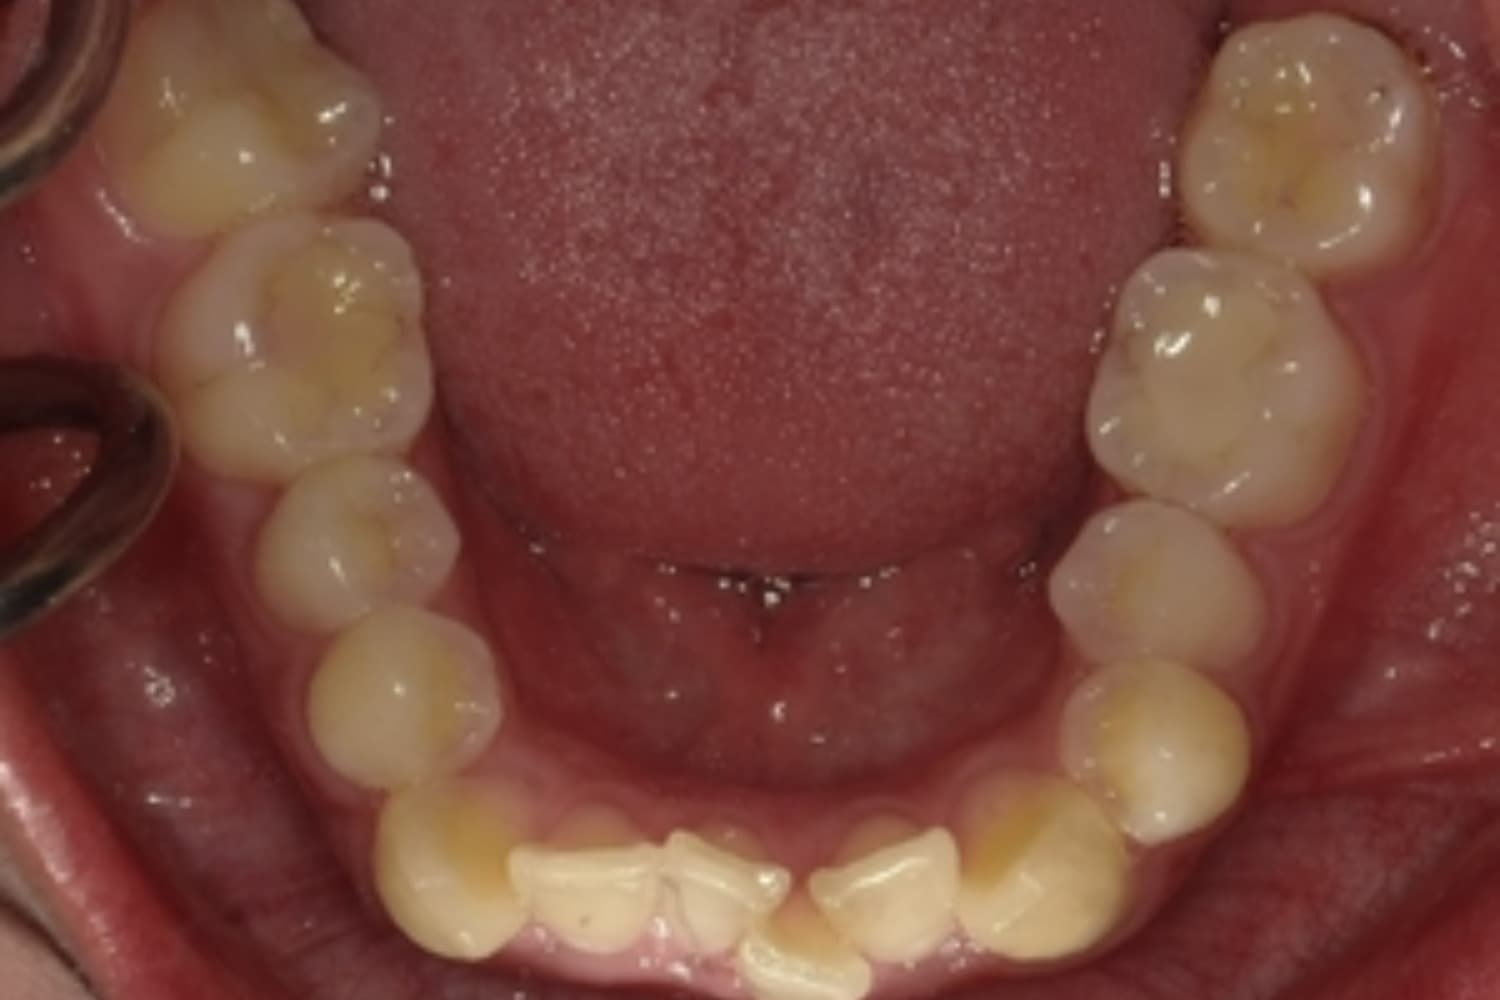

ガタガタとした歯並びや八重歯(1)

Before

After

ガタガタとした歯並びや八重歯をマウスピース矯正(インビザライン)にて治療

主訴

下の前歯のガタガタが気になる

治療期間

2年5カ月

費用

90万円

副作用・リスク

・矯正治療による歯の動きには個人差があり、想定より治療期間が延びることがあります。 ・矯正治療で歯を動かす際に痛みをともなうことがあります。 ・指示された通りに保定装置を装着しないと、歯並びや噛み合わせの後戻りを引き起こす可能性があります。